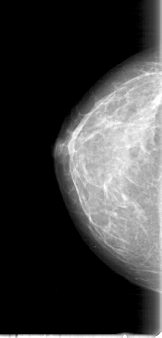

D_4000_1.RIGHT_CC

RIGHT_CC LINES 5056 PIXELS_PER_LINE 2416 BITS_PER_PIXEL 12 RESOLUTION 43.5 NON_OVERLAY